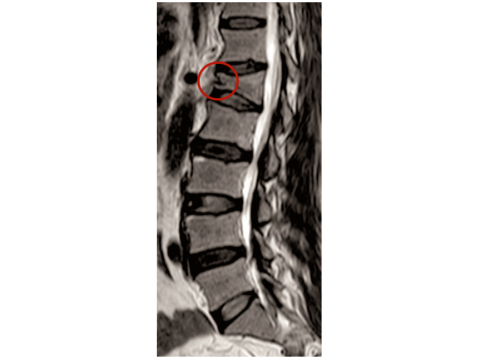

张振声的CT报告显示,其腰骶椎及双侧髂骨出现弥漫性钻孔样骨质破坏,核磁共振提示椎体骨折伴骨髓水肿。尹亚飞主任解释:“这种‘虫蚀样改变’是典型溶骨性病变表现,就像白蚁蛀空房梁,骨髓瘤细胞正在疯狂破坏骨骼结构。”经过骨髓穿刺、免疫固定电泳等系列检查,张振声被确诊为多发性骨髓瘤伴腰椎压缩性骨折,随即接受VRD方案(硼替佐米+来那度胺+地塞米松)化疗,首疗程后骨痛明显缓解。

核磁共振图像显示腰骶椎三角形态的“裂隙”,正是“虫蚀样骨质破坏”